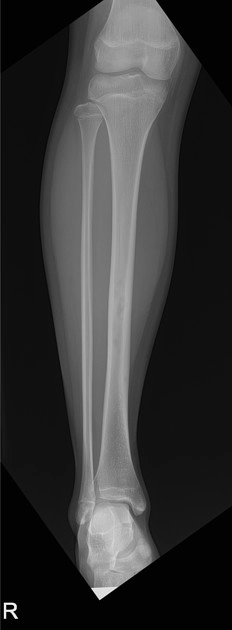

Loạn sản xơ xương (Fibrous dysplasia - FD)

Loạn sản xơ tạo xương (Osteofibrous dysplasia)

U xơ tạo xương (Ossifying fibroma)

U xơ không cốt hóa (Non-ossifying fibroma - NOF)